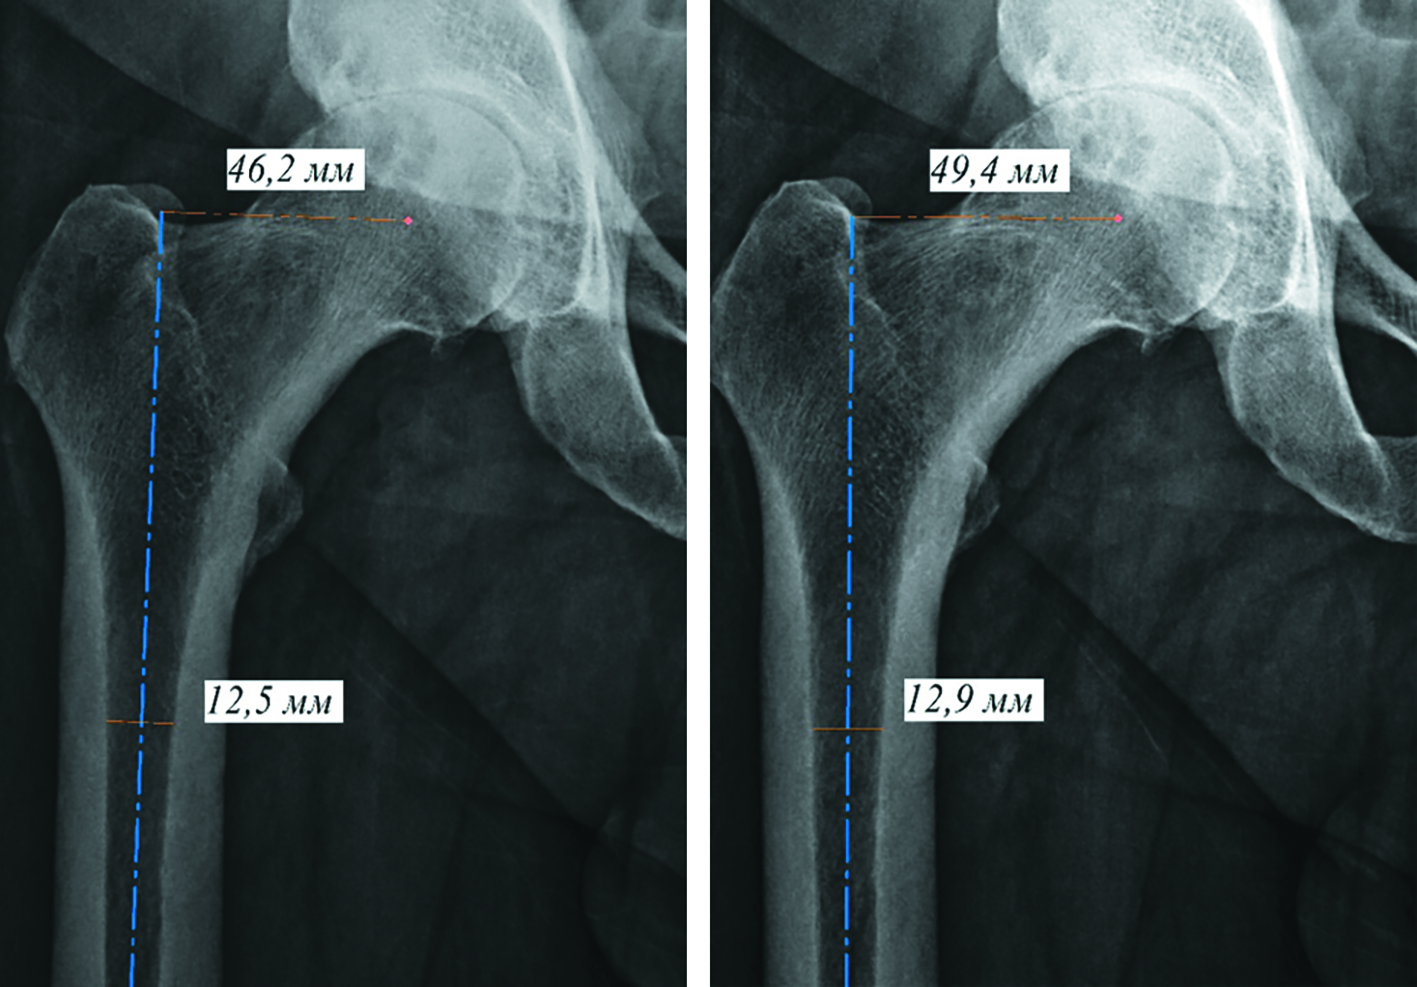

При ротации бедренных костей изменяются 3 параметра: шеечно-диафизарный угол, офсет и ширина костномозгового канала (рисунок 4).

Рисунок 4. Рентгенограммы тазобедренного сустава при различной ротации нижних конечностей (указаны величины ширины костномозгового канала и офсета): А – нейтральное положение стопы, Б – внутренняя ротация стоп 12 градусов.

Figure 4. Radiographs of the hip joint with different rotation of the lower extremities (the values of the width of the medullary canal and offset are indicated): А – neutral foot position, В – internal foot rotation of 12 degrees.